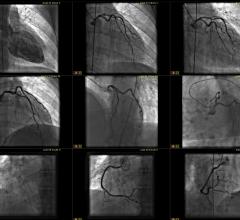

Cardiac PACS

This channel includes news and new technology innovations for cardiovascular information systems, CVIS, also called cardiac PACS. These cardiac reporting systems connect to the EMR and the hemodynamic system.